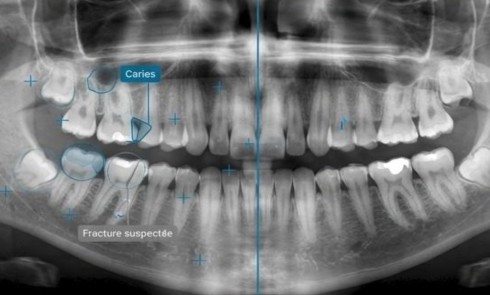

Santé publiqueAlors que l’American Heart Association (AHA) propose aux praticiens américains de dépister l’hypertension et les maladies cardiovasculaires au fauteuil, en intégrant la mesure de la tension artérielle aux visites de routine, une étude publiée en ligne dans le Journal of Dentistry le 20 février met en évidence le rôle potentiel des chirurgiens-dentistes dans le repérage précoce du diabète et du…

Maladies parodontales, diabète et convention

Le lien bidirectionnel entre les maladies parodontales et le diabète est déjà bien établi. Le diabète est un vrai problème de santé publique et le nombre de personnes atteintes ne cesse d’augmenter au niveau mondial. Le patient diabétique a trois…